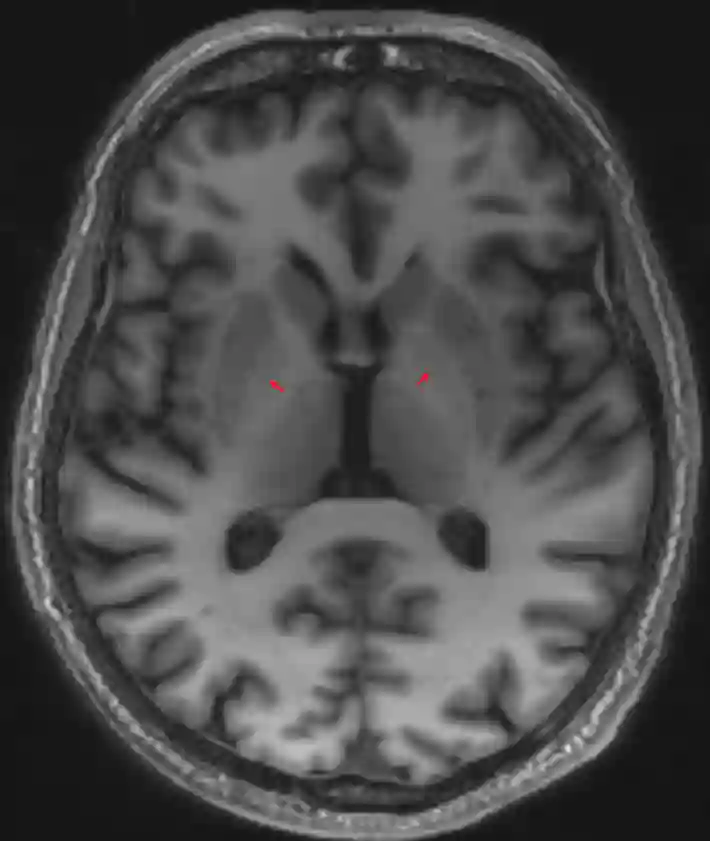

Globus pallidus MRI

Darstellen des Globus pallidus (roter Pfeil) in einer axialen MDEFT MRI Sequenz.